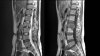

MRI : 염증 조직의 파급 정도를 알기 쉽습니다.

MRI : 척추 결핵(Spinal tuberculosis)

MRI : 척추 결핵(=Tuberculous spondylitis with large prevertebral abscess)